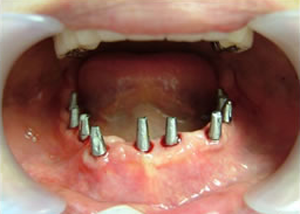

下はチタンの土台が10本入りました。

15.下の土台は平行性あわせて削ったところです。